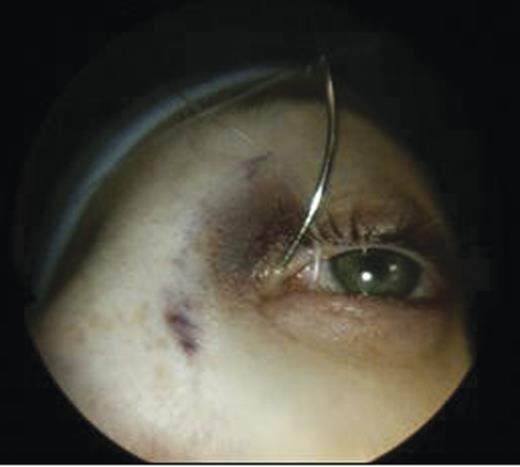

Clinical examination revealed a small cystic swelling in her left medial canthus (Fig. 1). There was no discharge on pressure, mild tenderness was elicited and the swelling was not compressible. The rest of the eye examination was normal with a visual acuity of 6/6 in both eyes.

The puncti were probed (Fig. 5) and fluorescein dye instilled with no dye outflow to the left inferior meatus. It was not possible to pass the probe through the upper punctum so a mini-monoka DCR stent was inserted and secured (Figs. 6 and 7). Chloramphenicol eye drops were instilled.